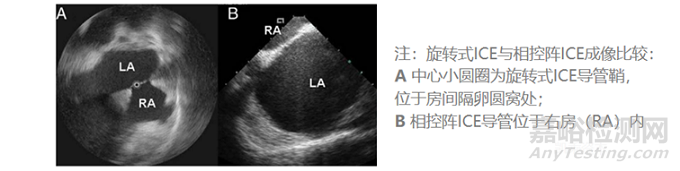

ICE使用5~12MHz的超聲頻率,理論最高分辨率可以達(dá)到0.1mm、且同時(shí)具有最高16cm的心內(nèi)穿透成像深度。常見的2D ICE導(dǎo)管分為單陣元旋轉(zhuǎn)超聲導(dǎo)管、電子相控陣列超聲導(dǎo)管兩類,目前后者在臨床上更為常用。目前ICE導(dǎo)管直徑為8~10Fr。

就2D ICE來說,相控陣ICE相比單陣元旋轉(zhuǎn)ICE具有以下優(yōu)勢(shì):更深成像深度、獲取多普勒血流彩超的能力。相控陣ICE因而在2D ICE當(dāng)中更受青睞。